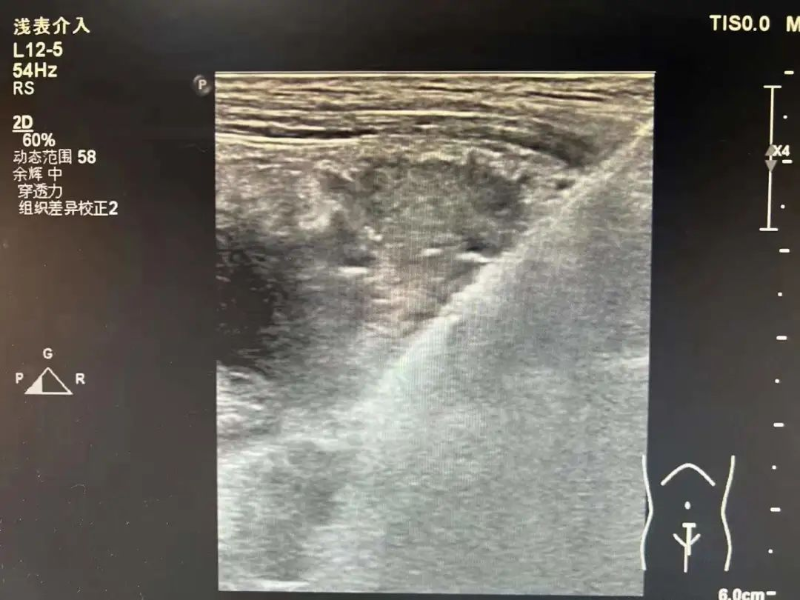

無獨有偶,3月16日,林伯伯(化名)四天前開始出現陣發性雙側胸痛,并伴有咳嗽、咳痰,遂到我院就診。門診檢查胸部增強CT顯示右肺上葉占位,疑是原發性支氣管肺癌,收治入院。

為進一步診斷病情,3月17日在陳勇輝超聲引導下,超聲醫學科蔣朝霞主任醫師為林伯伯進行肺腫瘤穿刺活檢。超聲引導下以右肺腫瘤最清楚處為目標,用穿刺針沿著引導線刺入,通過針尖穿越腫瘤觸發活檢槍進行活檢。穿刺后,林伯伯無不適。我院超聲醫學科成功完成穿刺活檢,為患者進行專科治療做“最強輔助”,充分體現了我院超聲醫學科能力水平的綜合提升,讓患者能就近就醫、就近診斷,為患者減輕看病就醫經濟負擔和解決奔波勞碌的問題。